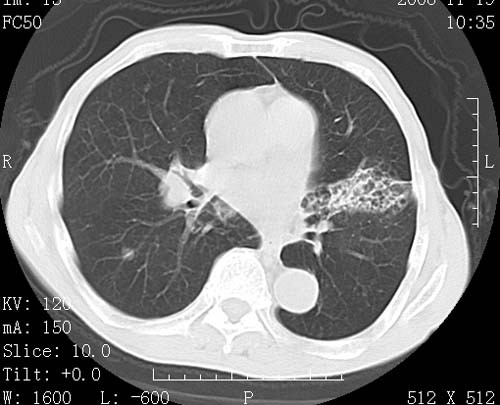

标题: CT16691:m 67 胃镜确诊食管下段及贲门癌 [打印本页]

标题: CT16691:m 67 胃镜确诊食管下段及贲门癌

术前查体,双肺部结节是转移?结核?请点评

1)符合食管癌表现。2)两肺及纵隔淋巴结多发性转移瘤。3)左肺上叶舌段及两肺下叶炎症感染。

食管癌伴双肺转移,评述:肺部毛细血管网丰富,全身血液均快速流经肺部,癌细胞容易过滤定植,形成转移瘤,影象特点为以毛细血管末梢为中心的结节灶,边缘光滑锐利,少见有中心空洞着,不同来源的转移瘤可有各自特点,如甲状腺癌为双肺弥漫性微结节,本例有原发灶,双肺影象灶典型,左肺舌段条带状网格样伴胸膜天幕征,可视为癌性淋巴管炎。

左肺舌段有斑点钙化灶,能否说明是结核而不是转移?如果是转移将放弃手术改成化疗,如果是结核将考虑择期手术